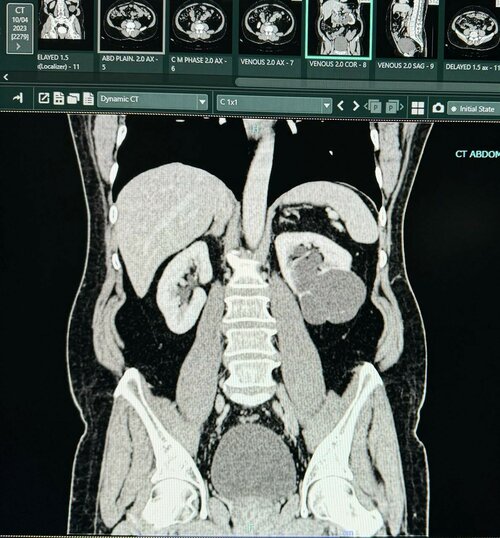

Robotic-Assisted Partial Nephrectomy by Dr. Bhoopat Bhati in Pune

Dr. Bhoopat Bhati, a renowned Urologist in Viman Nagar, Pune, successfully treated a 57-year-old female patient with a right kidney tumor using Roboti...